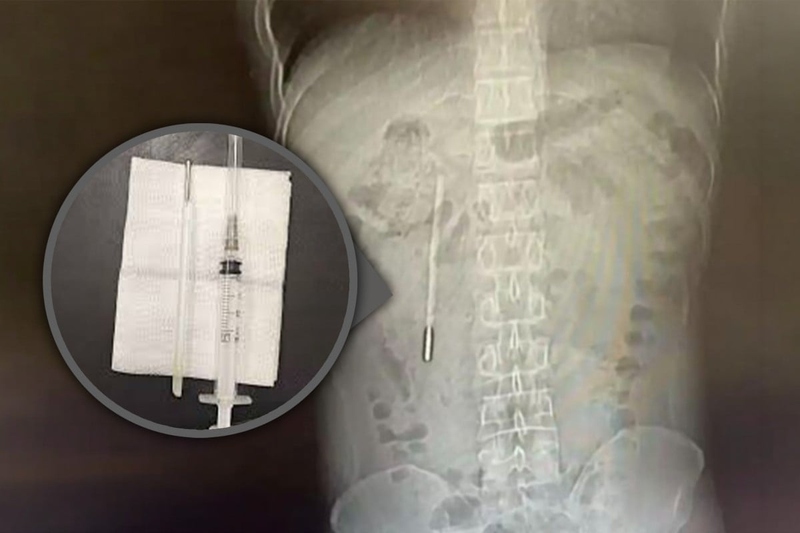

Nhận thức được mức độ nghiêm trọng của ca bệnh, các bác sĩ phẫu thuật đã nhanh chóng triển khai một ca mổ khẩn cấp. Quá trình can thiệp y tế để lấy dị vật ra khỏi cơ thể chỉ diễn ra trong vòng hai mươi phút ngắn ngủi nhưng lại đòi hỏi sự tập trung cao độ.

Đây được xem là một ca phẫu thuật cực kỳ tinh tế và phức tạp do chiếc nhiệt kế đã bị lưu lại bên trong cơ thể người bệnh trong một thời gian quá dài. Thêm vào đó, vị trí của nó nằm rất gần với các ống mật của Vương, tạo ra một rủi ro đáng kể về việc làm tổn thương lớp thành ruột xung quanh trong quá trình di chuyển dị vật.

Rất may mắn, thiết bị được lấy ra vẫn còn giữ được hình dạng nguyên vẹn ban đầu, mặc dù các vạch đo nhiệt độ in trên thân nhiệt kế đã bị mờ nhạt đi theo thời gian do tác động của môi trường dịch vị.

Các bác sĩ tại bệnh viện liên kết đầu tiên thuộc đại học y khoa Ôn Châu đã phẫu thuật khẩn cấp hai mươi phút để lấy dị vật.